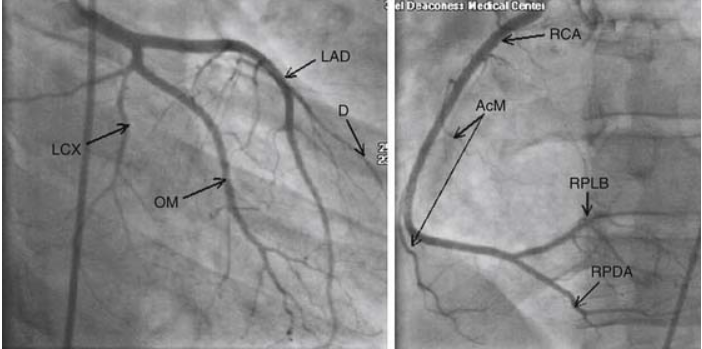

Angiography is an essential diagnostic and therapeutic modality in field of cardiology. The obstruction in vasculature of the heart is identified and relieved through angiography. The attached image shows the left coronary arteriogram. Contrast is used to define the vasculature. The image demonstrates the left main artery and its terminal branches i.e., left anterior descending artery and left circumflex artery. In some cases, an additional branch i.e., ramus intermedius may be present. Reference: https://thoracickey.com/coronary-angiography-valve-and-hemodynamic-assessment/ Image via: https://thoracickey.com/coronary-angiography-valve-and-hemodynamic-assessment/